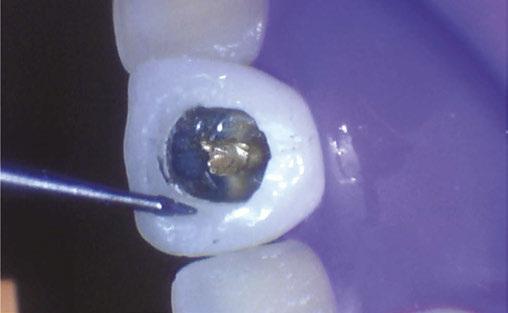

Case 1: Pre-op and diagnosis: A 68-year-old female presented with localized vestibular swelling buccal to tooth No. 30. No. 30 had been symptomatic for a few days, but the swelling started to alarm the patient and caused her to seek treatment. Upon evaluation, No. 30 was diagnosed as necrotic pulp with acute apical abscess. Two treatment options were discussed with the patient: 1) Tooth No. 30 non-surgical root canal therapy or 2) Tooth No. 30 extraction. The patient elected tooth No. 30 non-surgical root canal therapy (NSRCT). A pre-op Small FOV CBCT revealed a heavily calcified pulp chamber and calcified canals and a radix entomolaris. The CBCT revealed PARL’s at the apex of the mesial, distal, and radix entomolaris roots with the lesion extending coronally into the furcation. The patient was advised before treatment that this would be a very challenging case, and No. 30 NSRCT would be given a guarded prognosis, but she chose to proceed with No. 30 NSRCT. Treatment: No. 30 NSRCT, the patient was anesthetized with 68 mg Lidocaine with 0.034 mg EPI via IAN and 68 mg Septocaine with 0.017 mg EPI via buccal infiltration. Rubber dam isolation was utilized, and access was prepared through the PFM crown. 4 canals were located and then immediately after identification of the canal orifices, a platform was created with Soundseal, and the GentleWave Cleanflow handpiece was utilized to help break up the calcified tissue and negotiate each canal, alternating between a pathfile to slowly negotiate the coronal half of the canals and then running the GentleWave CleanFlow Procedure Instrument for 30-40 seconds to remove the accumulated debris. By alternating between files and the CleanFlow with GentleWave, all 4 canals were negotiated to length, and patency was achieved. The final working lengths were between 23 mm-24.5 mm for all 4 canals. All canals were instrumented to a Master Apical File of 20/.04 and obturated with high-flow BC Sealer. By utilizing the GentleWave and High-Flow BC Sealer, the apical delta of the distal root was cleaned, disinfected, and obturated in ways that would not have been possible with traditional endodontic therapy. Post-op: The patient was called 24 hours after treatment and reported she was pain-free, the swelling had reduced, and she was doing well.

Case 2: Pre-op and diagnosis: A 52-year-old female presented with a chief complaint of pain to hot and cold. Pulpal sensitivity testing on tooth No. 31 revealed a lingering, aching response to thermal testing. A clinical exam revealed a small crack extending from the occlusal resin over the distal marginal ridge. Probing depths around No. 31 were all <3 mm. No. 31 was diagnosed symptomatic irreversible pulpitis with symptomatic apical periodontitis. A pre-op small FOV CBCT revealed No. 31 to have a C-shaped canal morphology. Two treatment options were discussed with the patient: 1) Tooth No. 31 non-surgical root canal therapy or 2) No. 31 extraction. The patient elected No. 31 non-surgical root canal therapy (NSRCT). Treatment: No. 31 NSRCT, the patient was anesthetized with 68 mg Lidocaine with 0.034 mg EPI via IAN and 68 mg Septocaine with 0.017 mg EPI via buccal Infiltration. Rubber dam isolation was utilized, and access was prepared. Due to the C-shaped canal morphology, only two canals could be identified. Prior to placement of the SoundSeal platform, a small amount of bonding agent was placed over the crack along the distal marginal ridge and distal portion of the pulp chamber. The SoundSeal platform was securely placed to create a vacuum seal. The two canals were negotiated to achieve patency by alternating rotary instrumentation and the GentleWave CleanFlow Procedure Instrument for 30-40 seconds to thoroughly debride the internal anatomy. The mesial canal was instrumented to a Master Apical File of 20/.04, while the distal canal to a 25/.04 Master Apical File. Due to the larger and more irregular canal morphology of the distal canal, various-sized gutta-percha cones were used to gauge the size to be used for obturation. The mesial canal was obturated with a Sealer-based obturation method with High Flow BC Sealer and a single 20/.04 master cone. The distal canal was obturated with High Flow BC Sealer and Warm Vertical Compaction. With the aid of the GentleWave and the CleanFlow Procedure Instrument, the C-Shaped canal anatomy was more deeply cleaned, pulp tissue more thoroughly removed, and this case was completed in a single visit which would have been much more difficult to accomplish with traditional endodontic therapy.